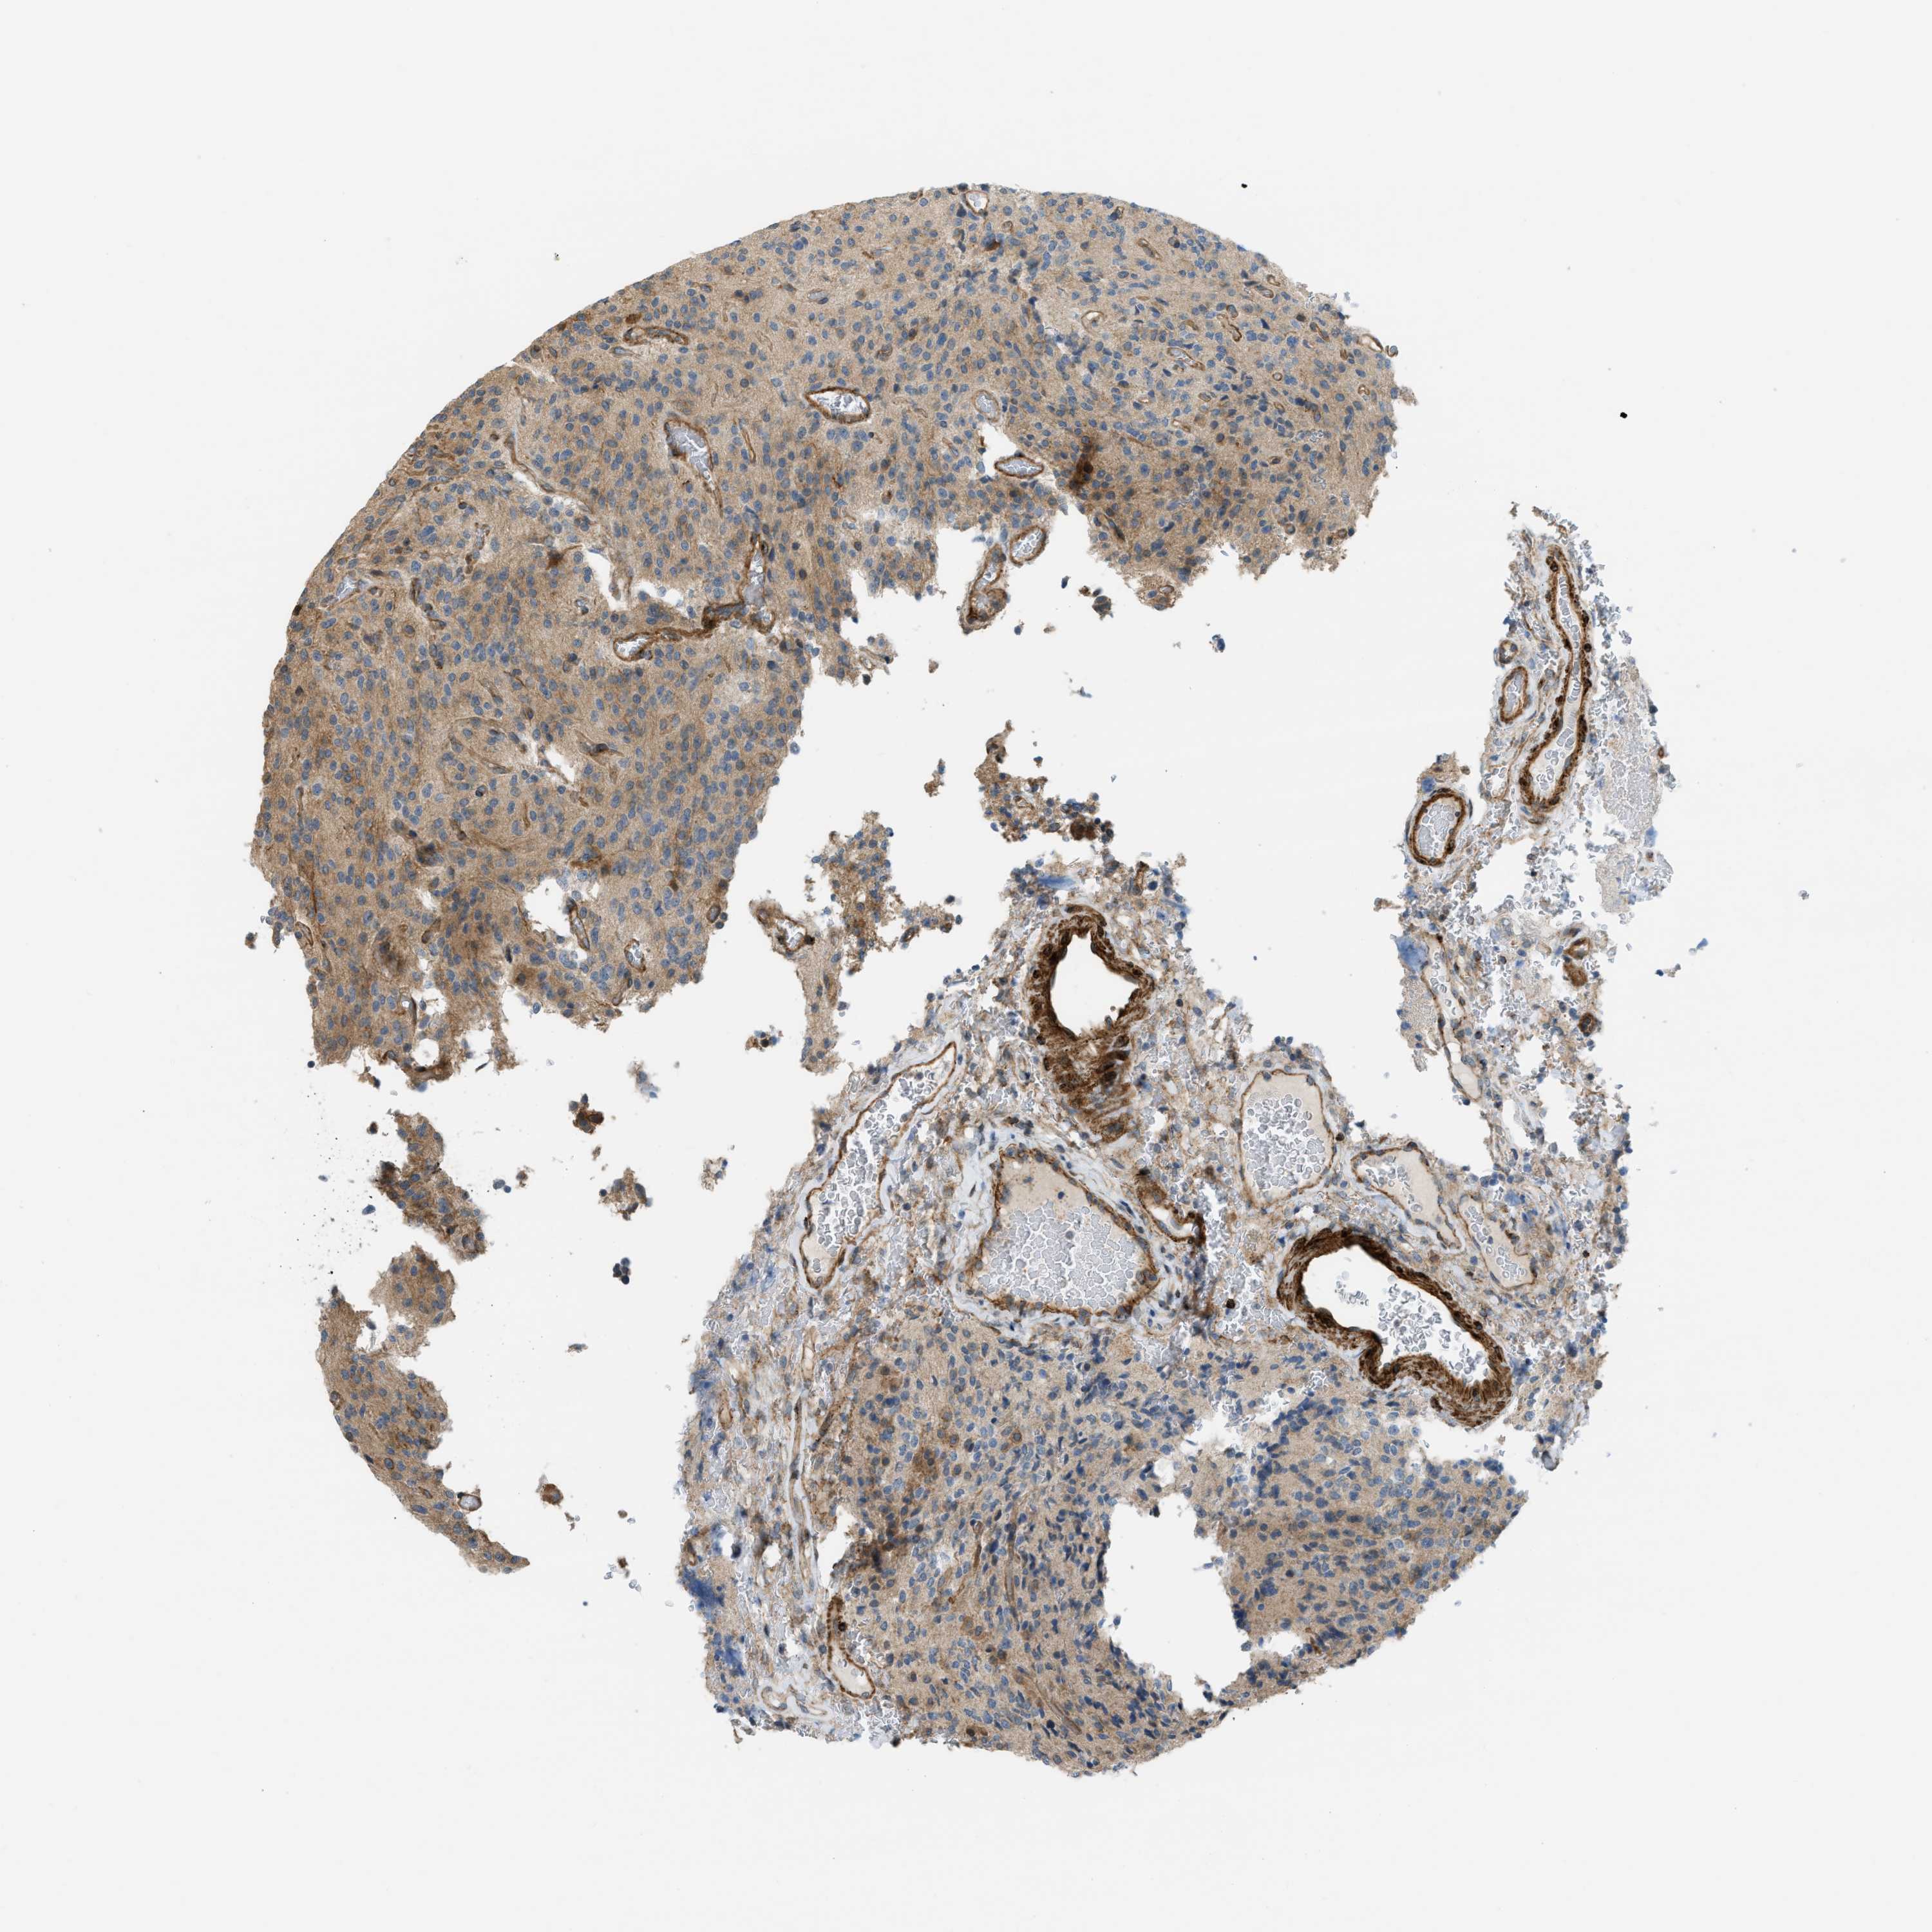

GLIOMA - Protein expressioni

A mouse-over function shows sample information and annotation data. Click on an image to view it in a full screen mode. Samples can be filtered based on level of antibody staining by selecting one or several of the following categories: high, medium, low and not detected. The assay and annotation is described here.

Note that samples used for immunohistochemistry by the Human Protein Atlas do not correspond to samples in the TCGA dataset.

Antibody stainingi

Antibody staining in the annotated cell types in the current human tissue is reported as not detected, low, medium, or high, based on conventional immunohistochemistry profiling in selected tissues. This score is based on the combination of the staining intensity and fraction of stained cells.

Each image is clickable and will lead to virtual microscopy that enables deeper exploration of all samples and also displays staining intensity scores, fraction scores and subcellular localization as well as patient and tissue information for each sample.

Antibody HPA018135

Staining

High

Medium

Low

Not detected

Intensity

Strong

Moderate

Weak

Negative

Quantity

>75%

75%-25%

<25%

None

Location

Nuclear

Cytoplasmic/membranous

Cytoplasmic/membranous,nuclear

Glioma, malignant, High grade

Glioma, malignant, Low grade